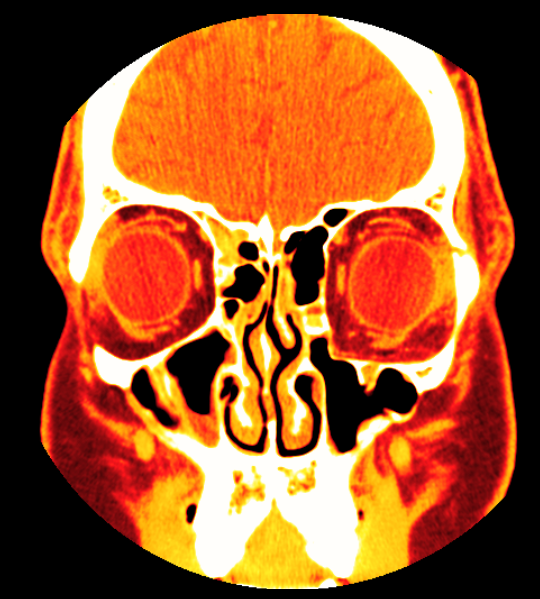

I had one surgery back in 2006 to put my eye back in the right place. It improved things slightly, but still left me with a droopy eye and some residual double vision. About six months later the surgeon did a CT scan, which ultimately looked like this:

The surgeon concluded at the time that the reason my eye was still droopy was because the orbital shape on the left side (which appears on the right in the CT image above) didn’t match the shape on the left. Effectively that leads to an increase in volume inside the eye socket which causes the eye to sink further in. Technically these effects goes by the names enophthalmos (sinking backwards into the eye socket) and hypoglobus (sinking downwards towards the sinus).